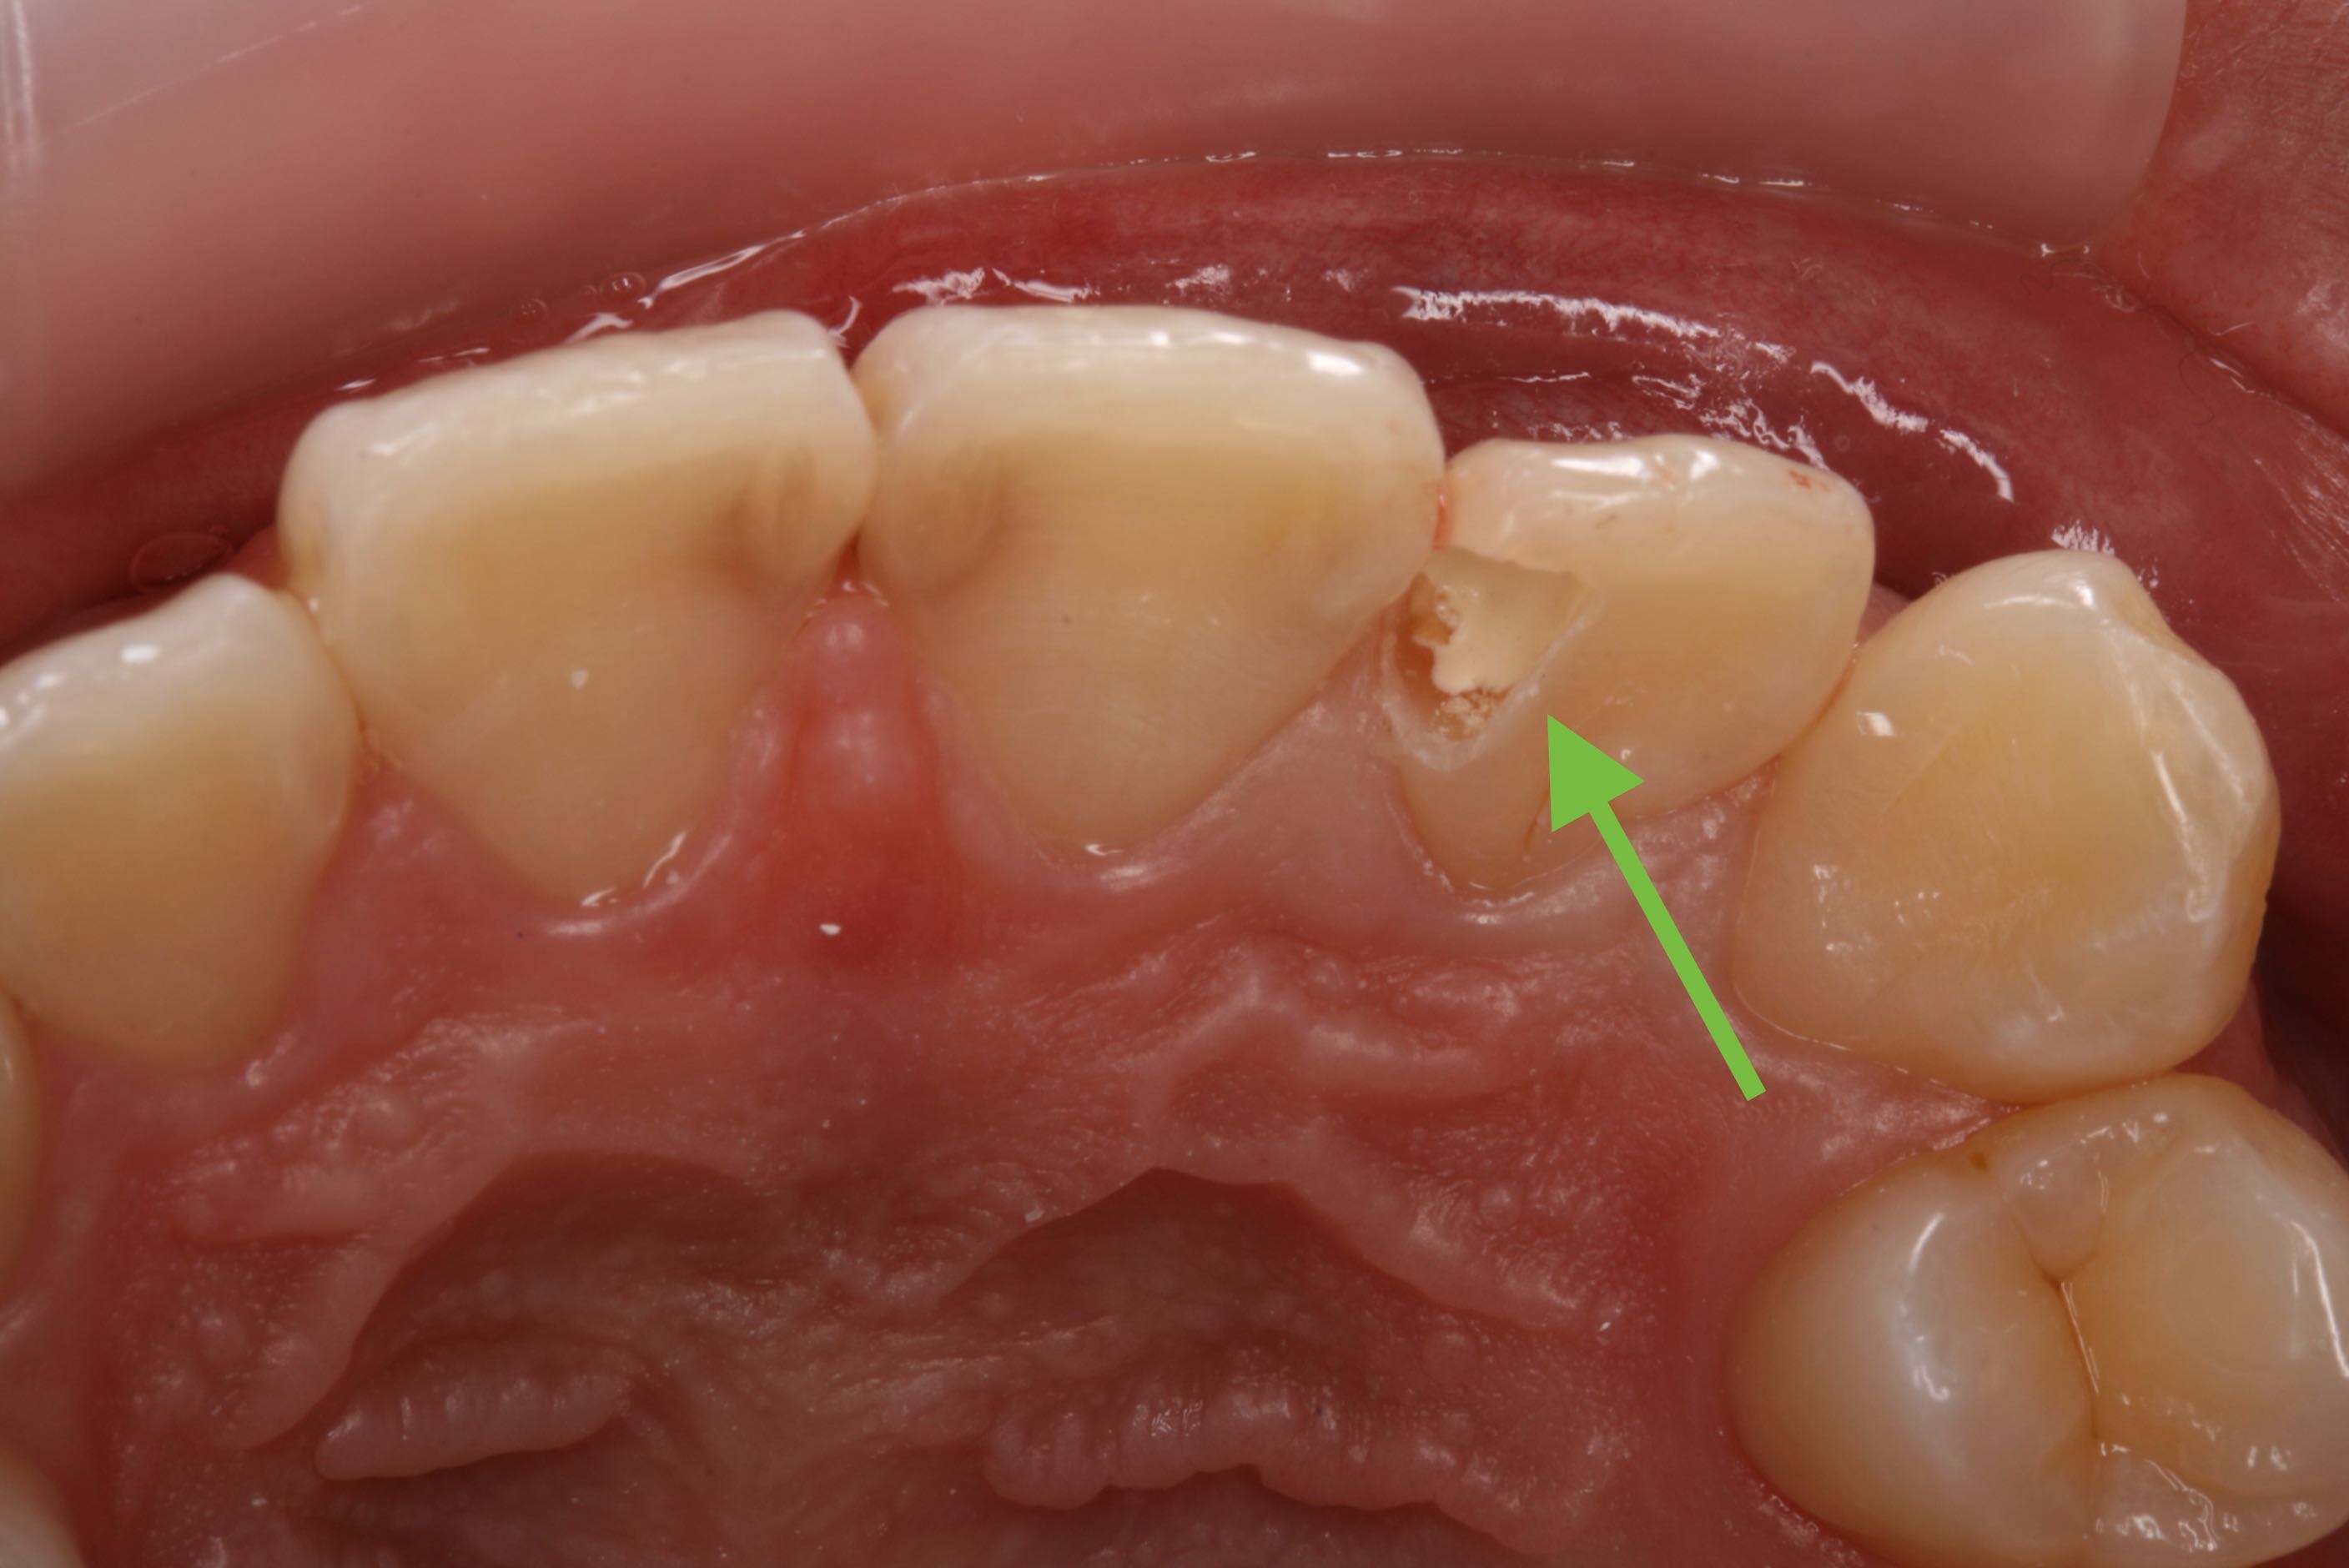

ティーンエイジャーの歯はまだ完全に成熟していないので、虫歯の穴は小さく見えても深く大きく広がりやすく、中の神経にまで進んでいることがあります。

虫歯をきれいに除去したときに、神経が見えたらいつも判断に悩んでしまいます。

そこで、意図的に虫歯を少し残して、間接的に神経を温存する薬を塗り、とりあえず歯に詰め物をして終了します。その後、定期的にレントゲンを撮影して、象牙質ができたか確認し、もう一度残してきた虫歯を取り除いて詰め物をします。薬は抗生物質(3MIX)よりもHYカルボテンポラリーソフトの方が学会のお墨付きもあり、予後が良いです。